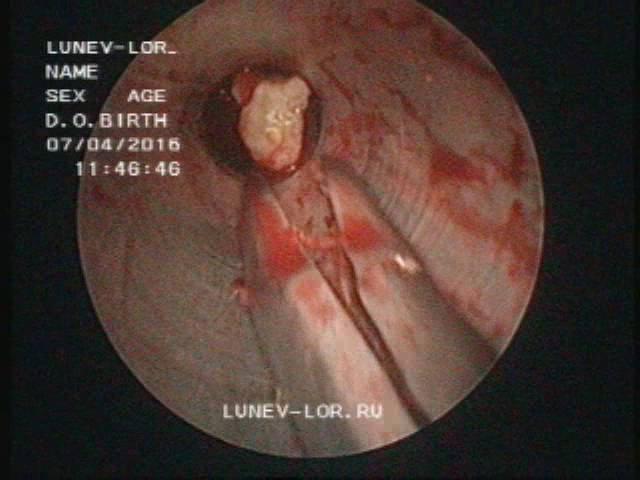

Микрогайморотомия удаление инородного тела верхнечелюстной пазухи 07042016

Микрогайморотомия удаление инородного тела верхнечелюстной пазухи 07042016

Лор врач Лунёв Андрей Владимирович